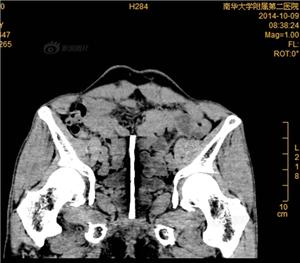

10月8日,湖南衡阳南华大学附二医院收治了一位奇葩患者,患者K某现年52岁,是一位单身男士。K某为了持久兴奋,将钢钉插入尿道,致钢钉上移滞留体内半年。

据患者讲叙,在半年多前的一次兴奋自慰时候,他突发奇想,想把自己的兴奋长期固定下来,于是用一个13公分的钢钉通过尿道慢慢地插入进去,可是随着时间的推移,钢钉不仅没有固定下他的兴奋,而且慢慢地往上走,居然在膀胱里面安营扎寨。